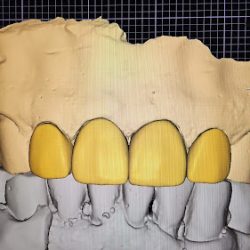

Fotos de Dental Vivo , Odontólogo Pediatra